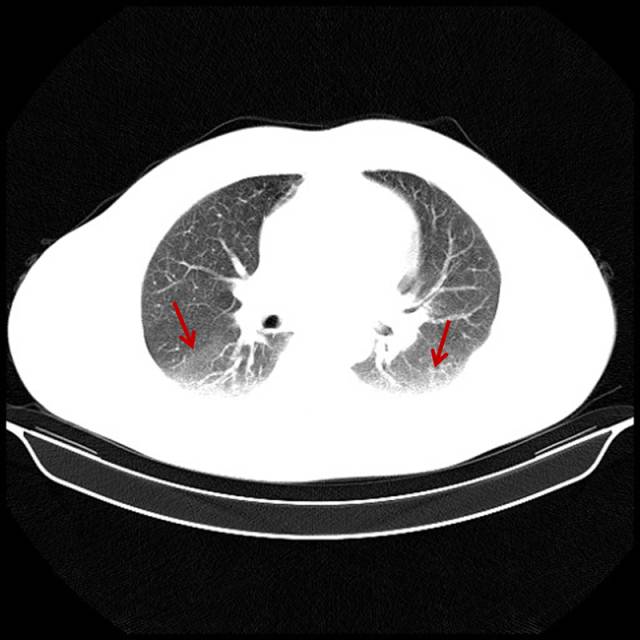

■吸烟导致的中度肺气肿

男,55岁,吸烟40年。